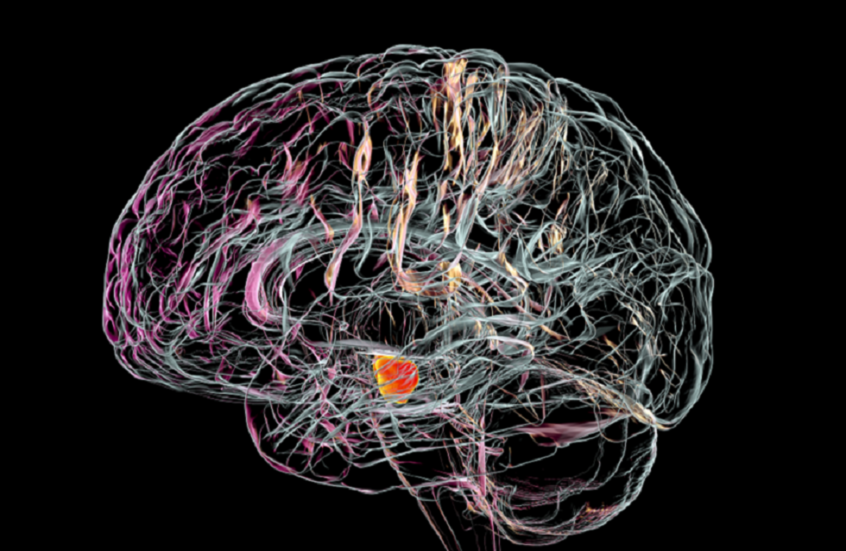

ويُعد مرض باركنسون اضطراباً عصبياً مزمناً يسبب الرعاش وصعوبات في الحركة والتوازن، إضافة إلى تيبّس العضلات ومشكلات في الكلام، وتزداد حدّة أعراضه تدريجياً مع مرور الوقت.